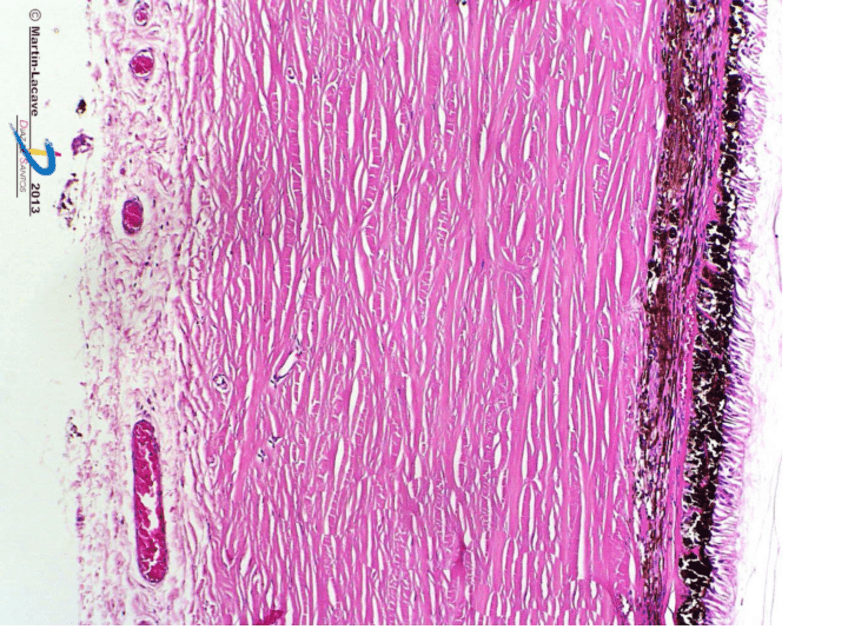

He publicado nuevos otros de 1º Histología Humana: Seminarios 2 parcial

Seminario-8.pdf

Seminario-9.pdf

Seminario-7.pdf

Seminario-10.pdf